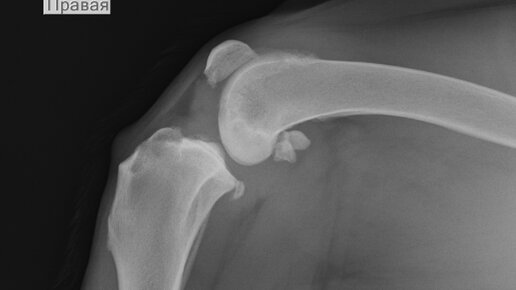

Вет Кабинет на Горбуновой, 10 (г.Киров)5 лет назадПодписатьсяБолезни суставов у собак.Термин «остеоартроз» объединяет группу заболеваний различного происхождения, но со схожим течением и исходом. В процесс болезни вовлекается не только суставной хрящ, но и весь сустав, включая кость, связки, капсулу сустава и мышцы...